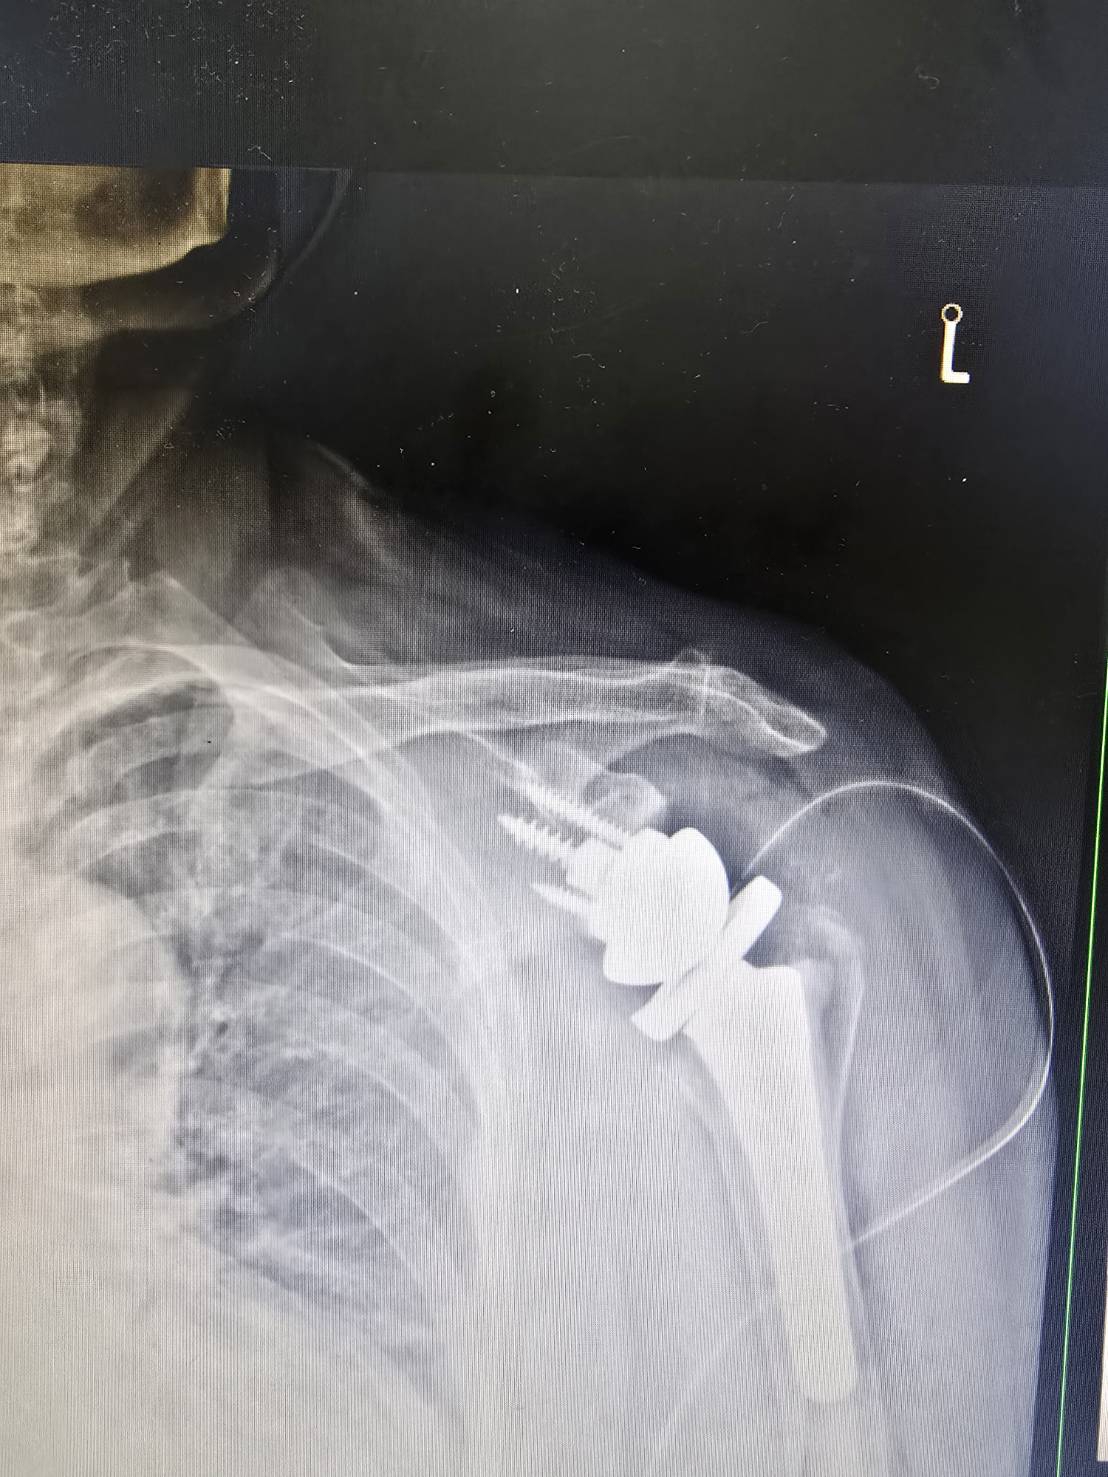

楊醫師最近也為一位這樣的病患,

完成了 Reverse Shoulder Arthroplasty——逆式人工肩關節置換手術。

事實上,當肩關節退化合併旋轉肌群嚴重損傷,傳統的肩關節置換往往無法解決問題——因為旋轉肌已經無力,裝了新關節也無法穩定運作。

這時候,逆式設計的巧妙之處就在這裡。

它把關節球與關節窩的位置對調,讓原本依賴旋轉肌的力學結構,改由三角肌來主導。

三角肌是肩膀最強壯的肌肉,即使旋轉肌嚴重耗損,三角肌依然能夠出力。

透過這個改變,肩膀重新獲得一個穩定的支點,疼痛減輕,活動範圍恢復,生活也跟著回來了。